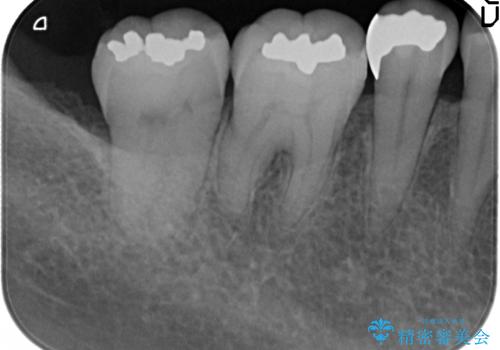

- 右下奥歯の古い銀歯をやり直したいといらっしゃった方の症例です。

銀歯を除去後、セラミックインレーにて修復しました。

当院のセラミックインレーはemaxという強度と審美性に優れた材料を使用しています。

またプレス方式でインレーを製作しているため、削り出しで製作するCADCAMより優れた適合性も持ち合わせており、虫歯が再発しにくい修復物です。